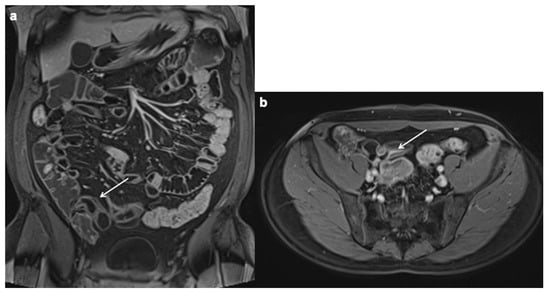

- Bruining, D.H.; Siddiki, H.A.; Fletcher, J.G.; Tremaine, W.J.; Sandborn, W.J.; Loftus, E.V., Jr. Prevalence of penetrating disease and extraintestinal manifestations of Crohn’s disease detected with CT enterography. Inflamm. Bowel Dis. 2008, 14, 1701–1706. [Google Scholar] [CrossRef]

- Booya, F.; Akram, S.; Fletcher, J.G.; Huprich, J.E.; Johnson, C.D.; Fidler, J.L.; Barlow, J.M.; Solem, C.A.; Sandborn, W.J.; Loftus, E.V. CT enterography and fistulizing Crohn’s disease: Clinical benefit and radiographic findings. Gastrointest. Radiol. 2008, 34, 467–475. [Google Scholar] [CrossRef] [PubMed]

- Baker, M.E.; Fletcher, J.G.; Al-Hawary, M.; Bruining, D. Interdisciplinary Updates in Crohn’s Disease Reporting Nomenclature, and Cross-Sectional Disease Monitoring. Radiol. Clin. N. Am. 2018, 56, 691–707. [Google Scholar] [CrossRef] [PubMed]

Fistula

| Inflammatory mass |

| Abscess |